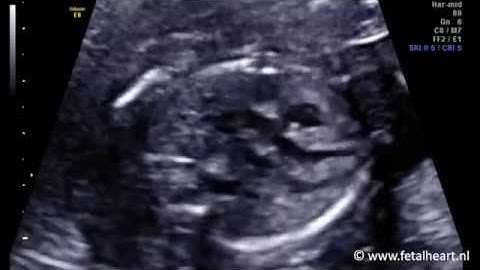

Fetal PCOM/PCA and Aplastic A1